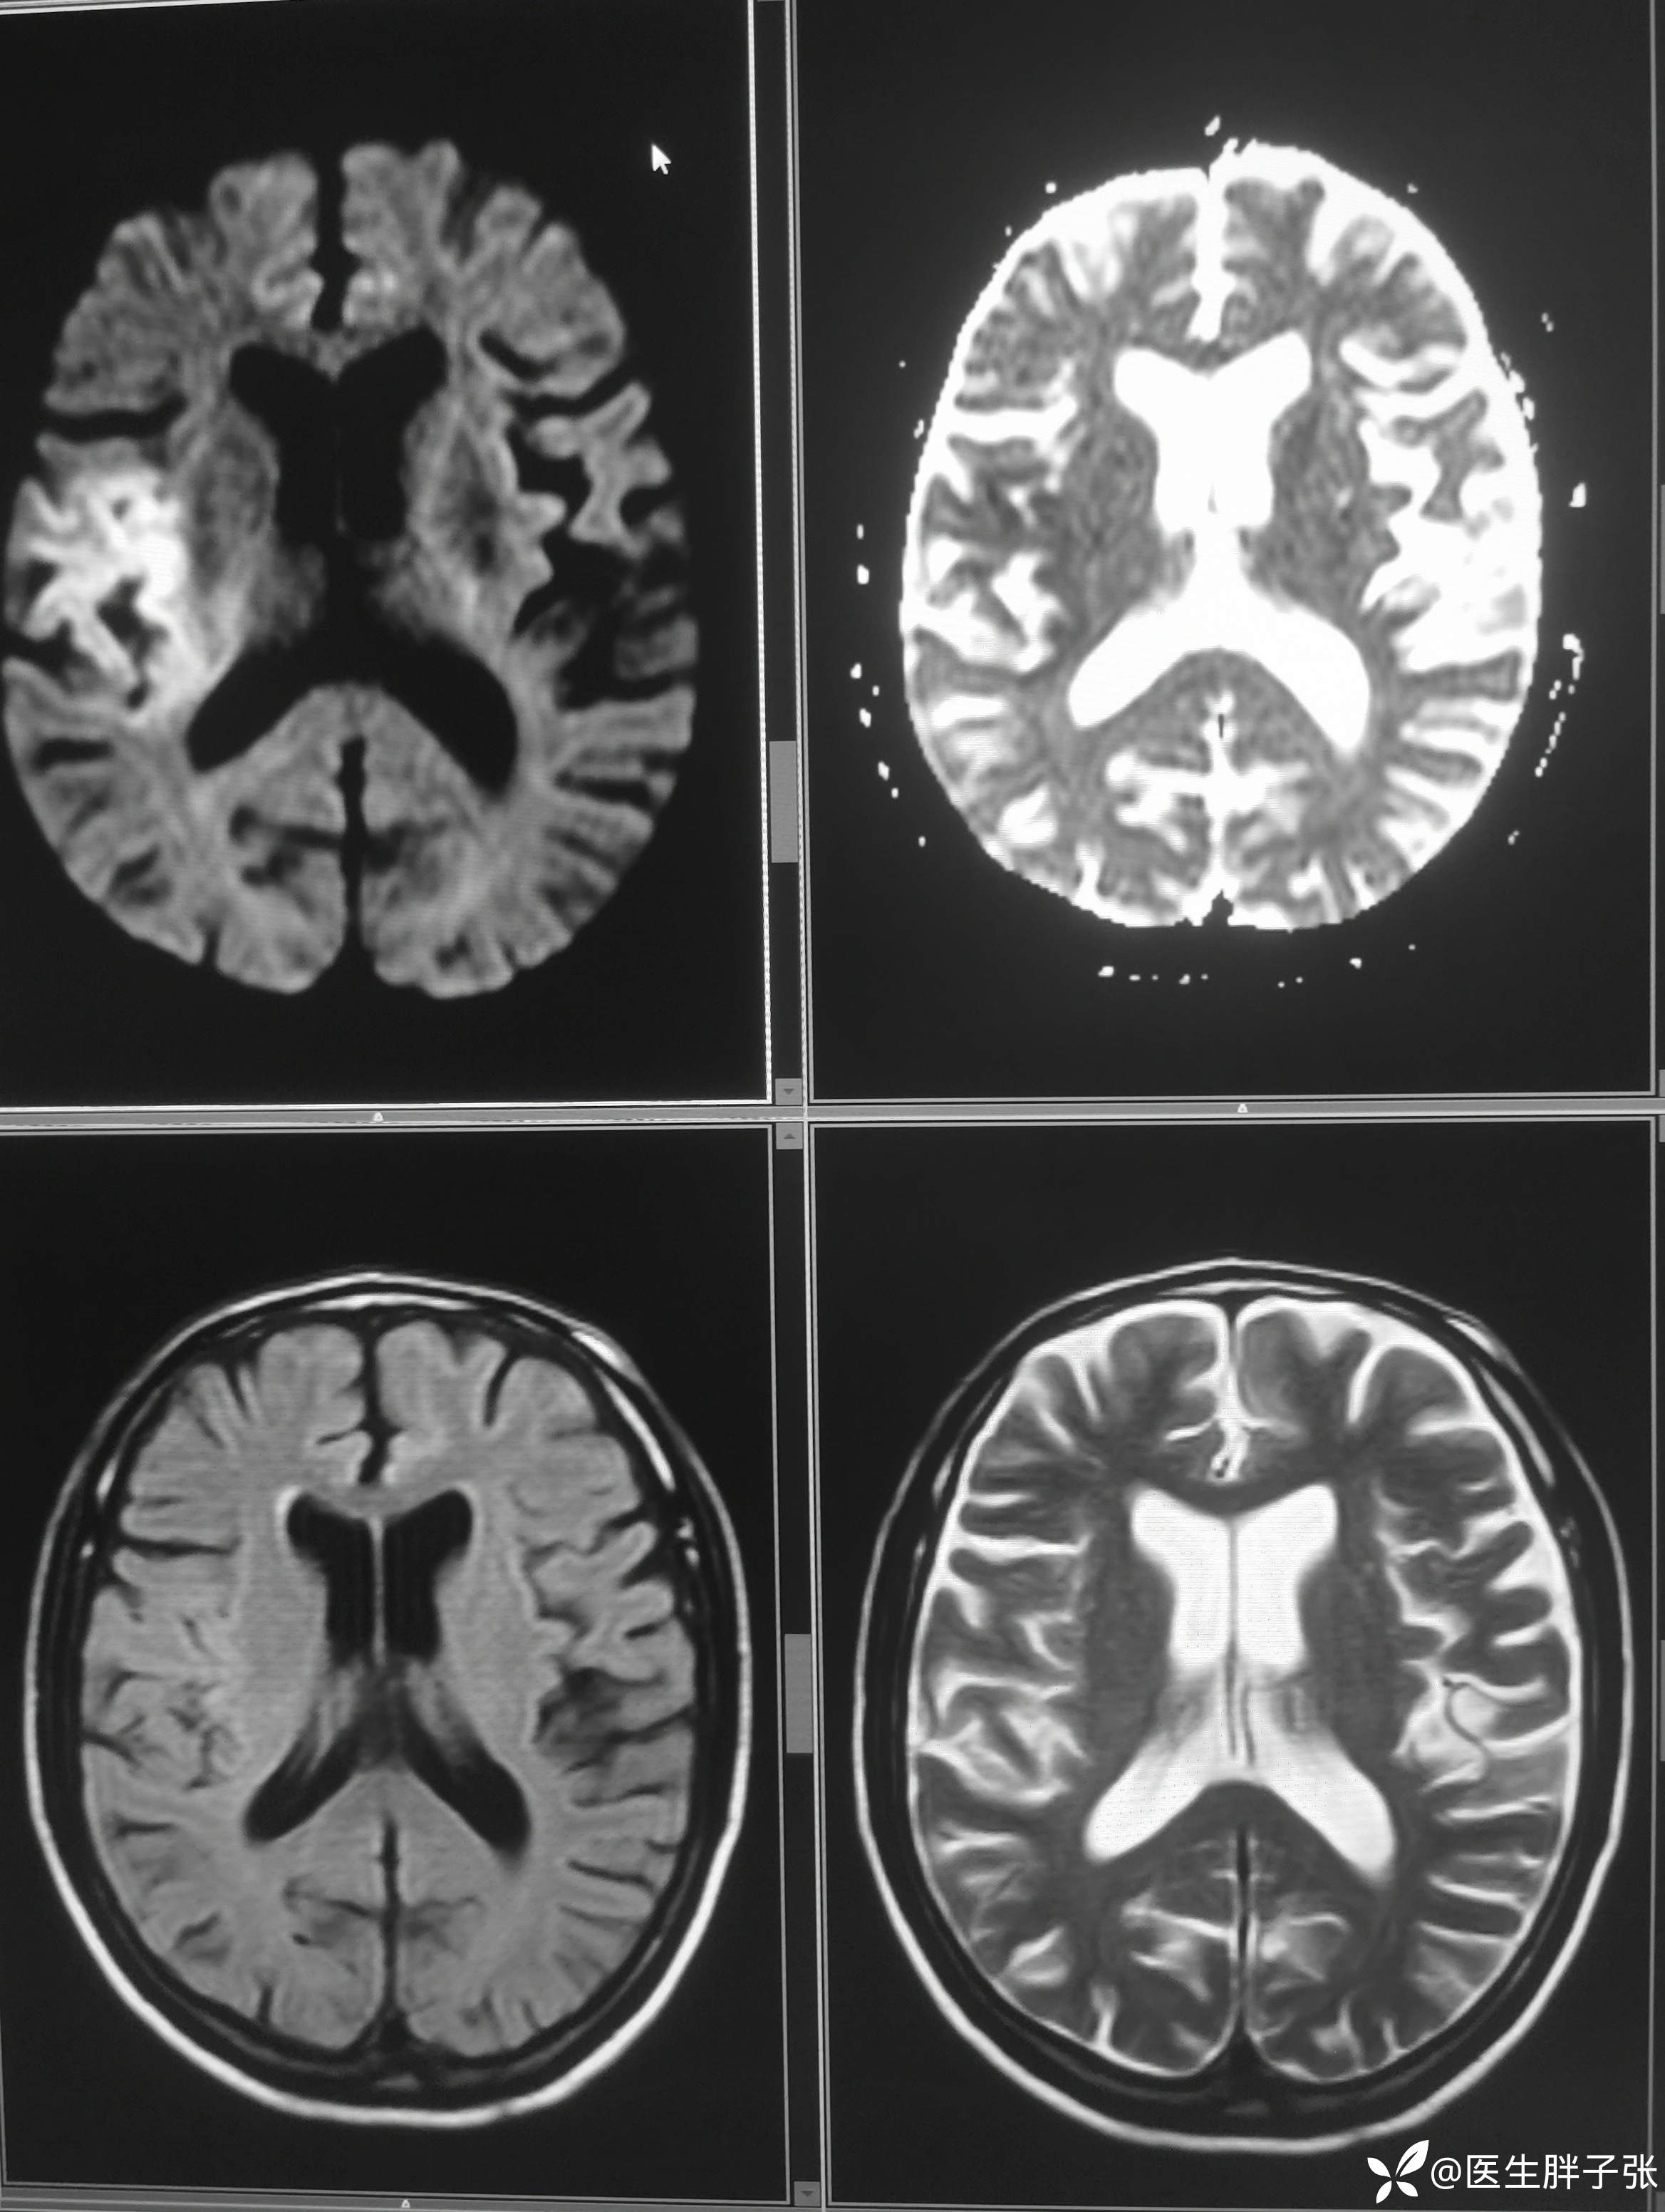

颅脑MR:右侧颞叶新近梗死灶;老年性脑改变;右侧大脑中动脉部分M2段及以远未见显示,建议头颈部CTA检查。

患者为醒后卒中患者,幸运的是恰好晨起交班的时候来院,恰好能查核磁,核磁提示存在DWI-FLAIR错配